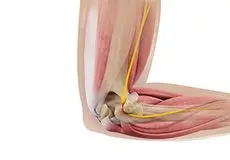

Ulnar Nerve Release

Ulnar nerve release, also known as ulnar nerve decompression, is a surgical procedure to treat a medical condition called ulnar nerve entrapment.